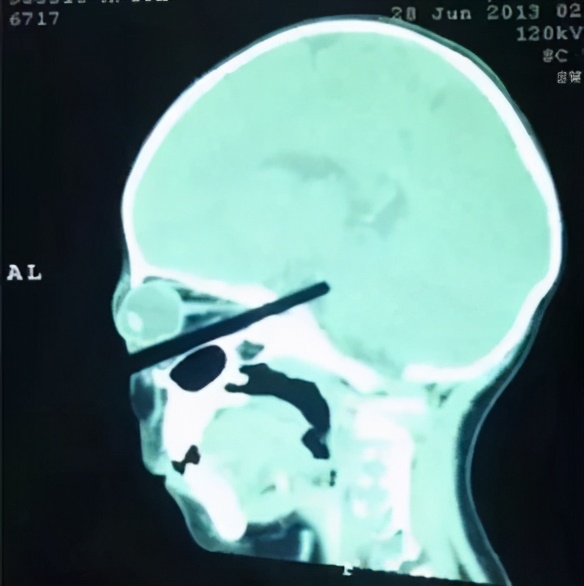

(△医生从宝宝气道中取出的异物)

11月12日,贵州荔波县一名1岁半的幼童在含筷子玩耍时不慎摔倒,筷子直接插入咽喉深处,并波及到了颈部食管、气管和其他邻近颈部的重要器官,随时面临大出血、大脑休克及窒息等生命危险!

无独有偶。2岁男宝用筷子插着玉米吃,妈妈下楼倒个垃圾的功夫,孩子就把筷子戳进了眼睛!